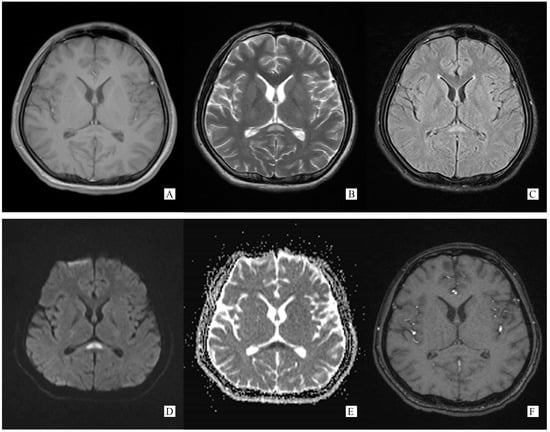

A total of 6 days after onset, on 3 November 2021, he turned to a higher-level hospital for further evaluation and treatment. Lumbar puncture showed CSF ICP 350 mmH2O, glucose 2.25 mmol/L, chlorine 118.2 mmol/L, and protein 1.27 g/L. WBC counts were normal. Cerebral MRI demonstrated an abnormal signal on SCC (Figure 1). Based on these results, he was considered as meningoencephalomyelitis, and was given ceftriaxone to anti-infective. However, there was no improvement in the condition.

Figure 1.

(Performed on 5 November 2021). (A) Axial T1 weight brain MRI image showing an oval hypointense lesion on SCC. (B) Axial T2 weight brain MRI image showing an oval hyperintense lesion on SCC. (C) Axial T2 flair weight brain MRI image showing an oval hyperintense lesion on SCC. (D) Axial DWI weight (b = 1000) brain MRI image showing an oval hyperintense lesion on SCC. (E) Axial ADC weight brain MRI image showing an oval hyperintense lesion on SCC. (F) Axial post-gadolinium T1-weighted brain MRI showing no enhancement on SCC lesion.

Generally, typical features of autoimmune GFAP astrocytopathy present as a linear, radial perivascular enhancement pattern on brain MRI, and central longitudinally extensive enhancement pattern on spinal cord MRI [7]. RESLES is typically classified into two patterns on MRI: type I is an isolated lesion on SCC, type II is a lesion in SCC expending to callosal fibers, cerebral white matters or anterior portion of corpus callosum. No matter type I or type II, lesions can be significantly shrunk or totally disappeared within a month, accompanied with the relief of symptoms [8]. In the MRI of our case, the lesion was located in the SCC, manifested a hypointense signal on T1WI and hyperintense on T2WI and DWI, reversibly, which is similar to type I RESLES, but unlike the typical autoimmune GFAP astrocytopathy.